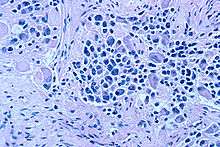

On microscopy, the tumor cells are typically described as small, round and blue, and rosette patterns (Homer Wright rosettes) may be seen. Homer Wright rosettes are tumor cells around the neuropil, not to be confused with pseudorosettes, which are tumor cells around a blood vessel.[25] They are also distinct from the pseudorosettes of an ependymoma which consist of tumor cells with glial fibrillary acidic protein (GFAP)–positive processes tapering off toward a blood vessel (thus a combination of the two).[26] A variety of immunohistochemical stains are used by pathologists to distinguish neuroblastomas from histological mimics, such as rhabdomyosarcoma, Ewing's sarcoma, lymphoma and Wilms' tumor.[27]

Neuroblastoma is one of the peripheral neuroblastic tumors (pNTs) that have similar origins and show a wide pattern of differentiation ranging from benign ganglioneuroma to stroma-rich ganglioneuroblastoma with neuroblastic cells intermixed or in nodules, to highly malignant neuroblastoma. This distinction in the pre-treatment tumor pathology is an important prognostic factor, along with age and mitosis-karyorrhexis index (MKI). This pathology classification system (the Shimada system) describes "favorable" and "unfavorable" tumors by the International Neuroblastoma Pathology Committee (INPC) which was established in 1999 and revised in 2003.[28]